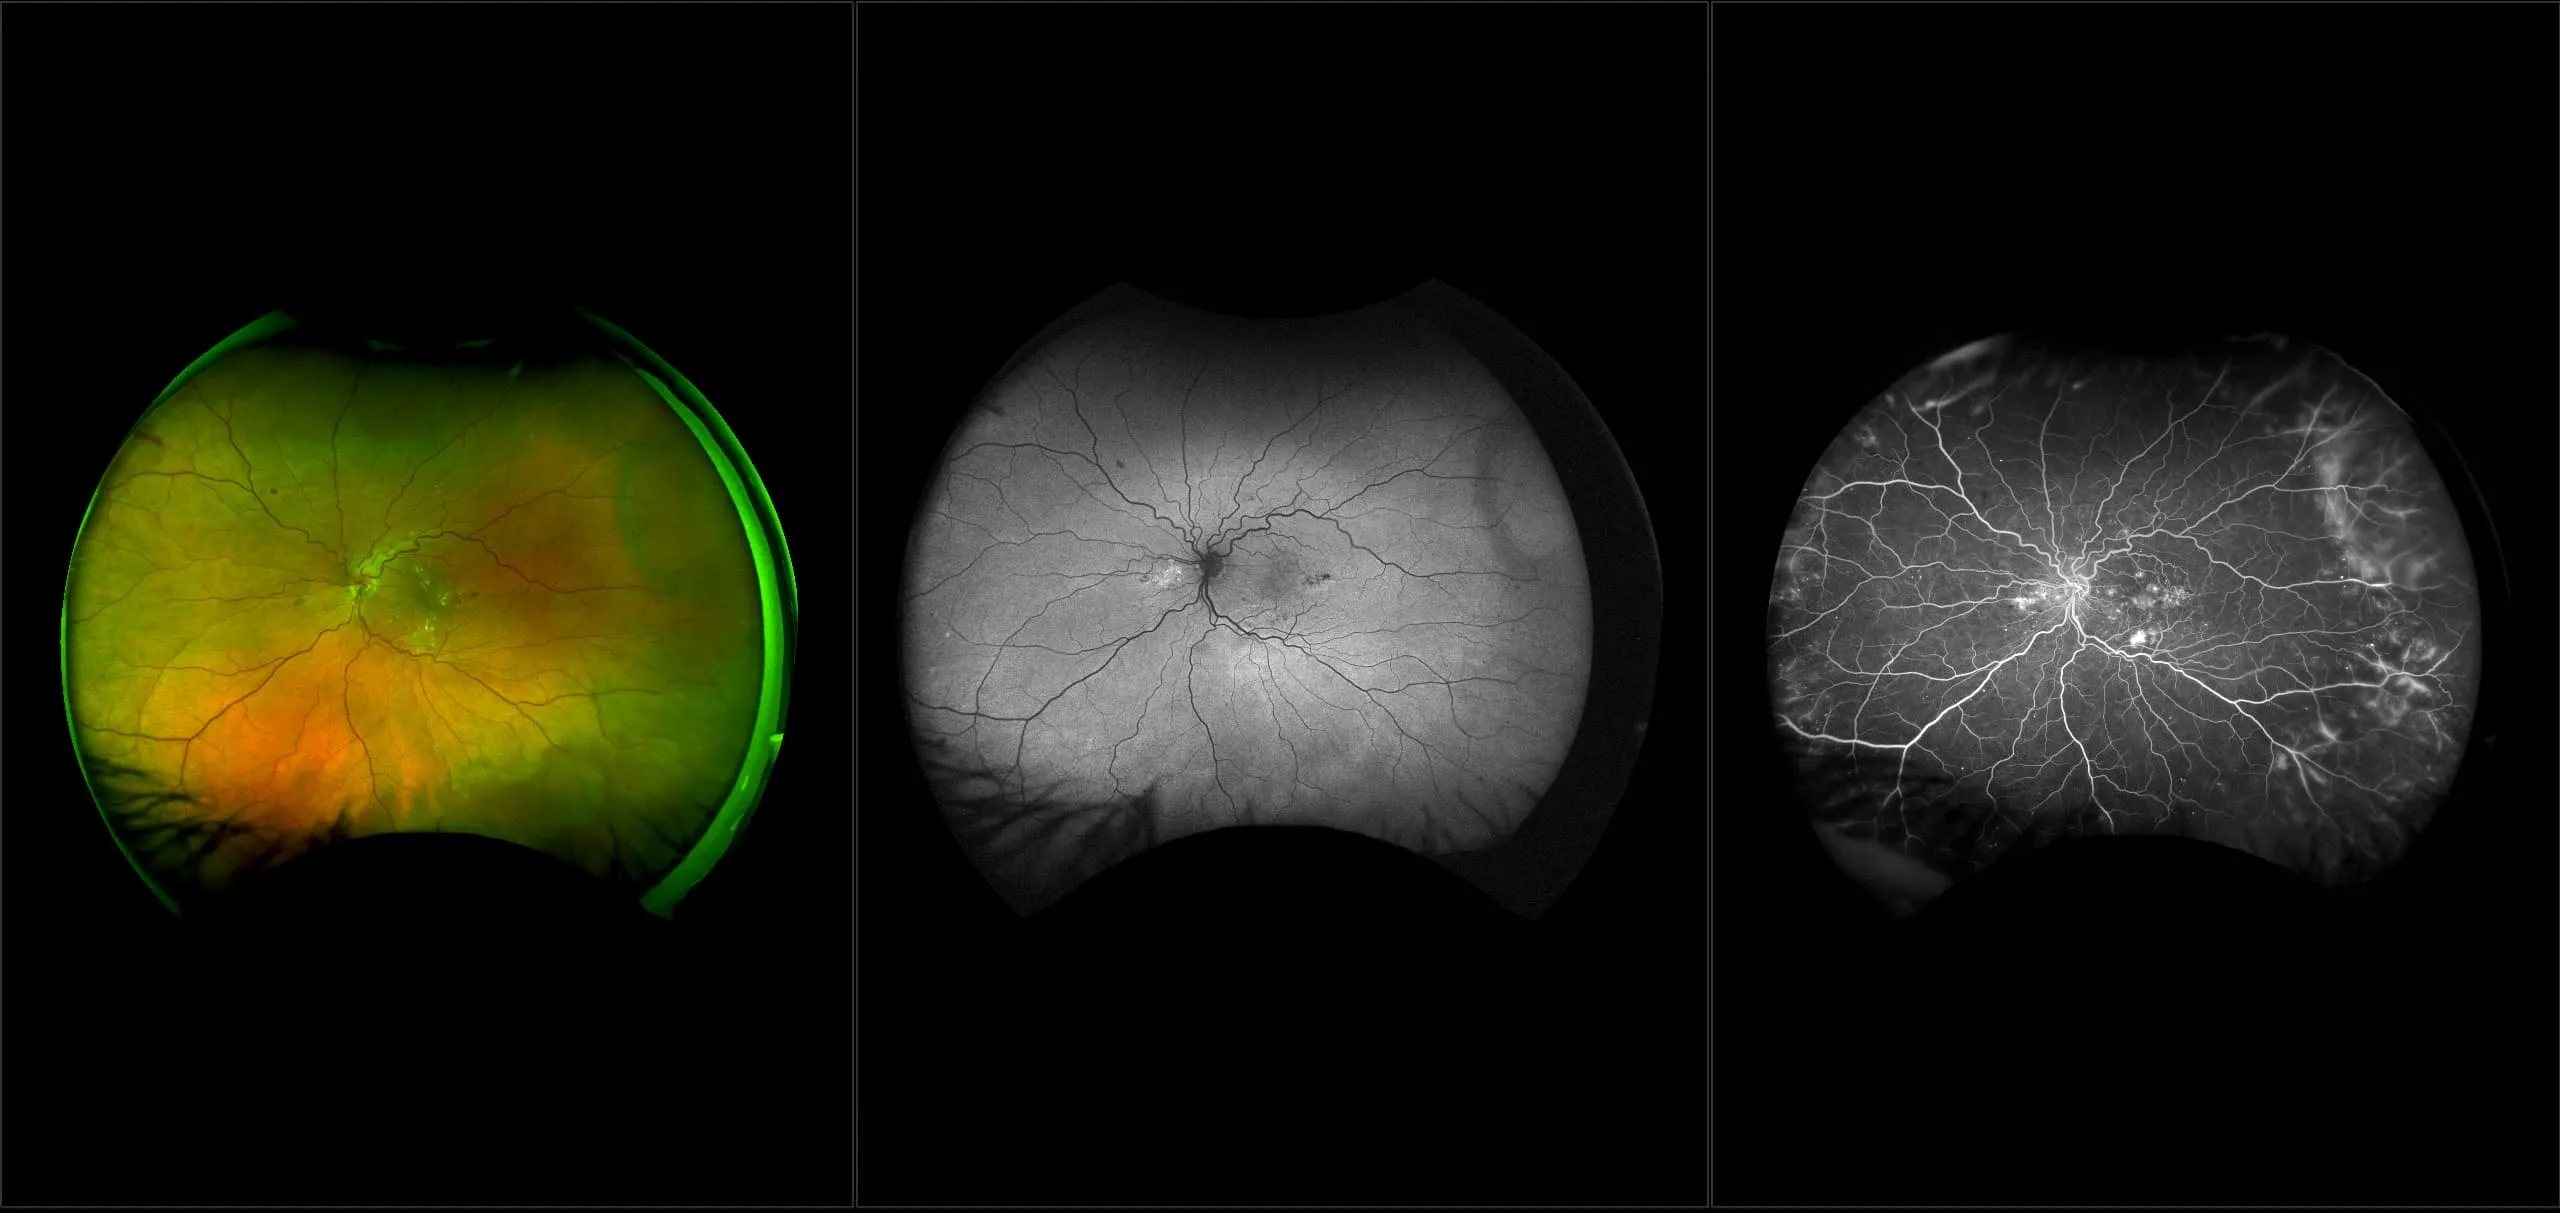

optomap® Recognizing Pathology

This material is designed as a searchable reference resource to support clinical decision-making. The information contained here should be used as general guidance when viewing optomap and OCT images from Optos devices. The differential diagnosis should be made under the direction of the responsible physician. These images were taken on the latest ultra-widefield optomap devices.

The Cases and Images

optomap Recognizing Pathology is searchable by pathology and/or optomap image modality. You may search by multiples of each selection. Each individual case is represented by the accompanying thumbnail image. Most cases include several different optomap image modalities. To view a full description of the case, please click on the thumbnail. Each image in the case will be made available through our OptosAdvance software which provides multi-dimensional visualization of digital images to aid in the analysis of anatomy and pathology. Support and pathology definitions can be found by selecting one of the buttons, above. Should you have questions, please complete the form below.